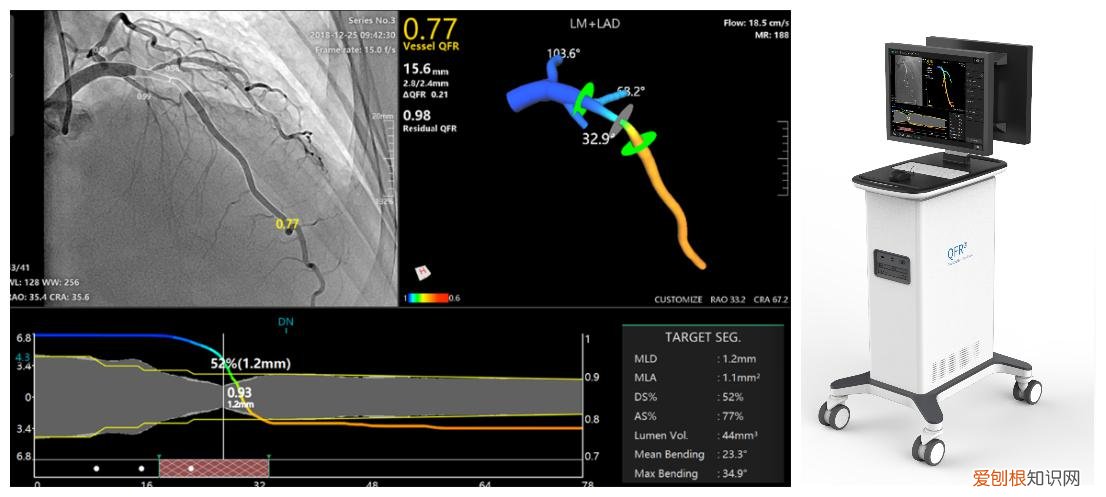

日前,在第一届上海市人工智能与冠脉生理学高峰论坛上,由我国科学家发明的全球首个AI-QFR冠脉定量血流分数检测仪正式发布,该项创新技术将有利推动我国乃至全球的广大冠心病患者的精准诊断和治疗 。

据悉,QFR定量血流分数检测仪是中国原创、国际首创、首个获国家药监局批准上市的国产FFR产品 。

该技术在全球范围内已完成2万多例临床验证,也是全球唯一完成大型随机对照临床试验(RCT)的无导丝FFR技术 。

新一代AI-QFR完美运用AI赋能,进一步拓展适应症 。仅需1幅造影、1步计算、1分钟内全自动完成冠脉主支与分支的FFR评估和PCI导航,诊断精度高达93% 。